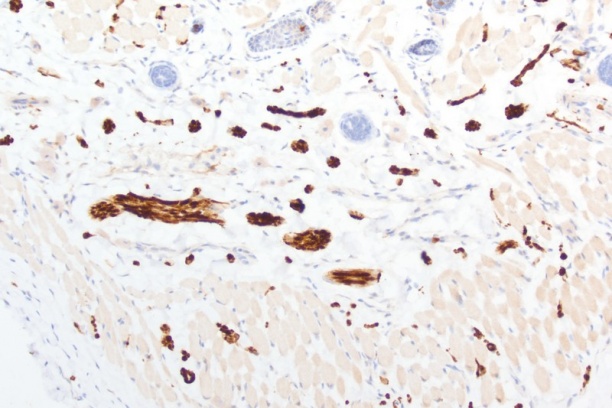

- Research histology including, immunohistochemistry and novel antibody development